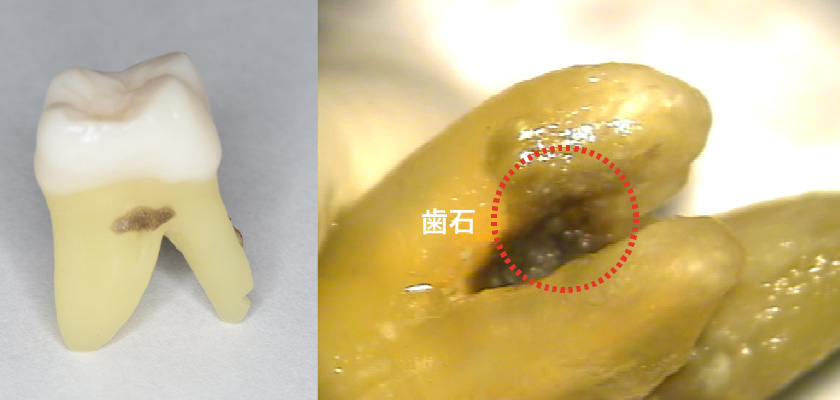

歯の分かれ目に一度、ばい菌や歯石が入り込んでしまうとその除去は困難を極めます。

仮にきれいにできたとしても、歯ブラシが行き届かないため、ばい菌の格好のたまり場となってしまいます。きれいにしやすい環境を作り確実に歯石やプラークを除去するために根を分割して治療する場合もあります。

二本や三本に分かれている根を分割して残す治療

タービンで歯を切断します。

状態の悪い歯根のみを抜歯します。

ブリッジを装着します。

左から二本目の歯は2根に分かれていて手前(バツ印)の根がダメになっています。

ダメになっている根を抜いて手前の根とブリッジでつなぎました。